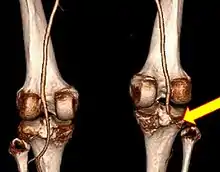

| Plain lateral X-ray of the left knee showing a posterior knee dislocation[1] | |

Plain X-rays, CT scan, ultrasonography, or MRI may help with the diagnosis.[2][11] Findings on X-ray that may be useful among those who have already reduced include a variable joint space, subluxation of the joint, or a Segond fracture.[5]

They may be divided into five types: anterior, posterior, lateral, medial, and rotatory.[4] This classification is based on the movement of the tibia with respect to the femur.[11] Anterior dislocations, followed by posterior, are the most common.[2] They may also be classified on the basis of which ligaments are injured.[2]